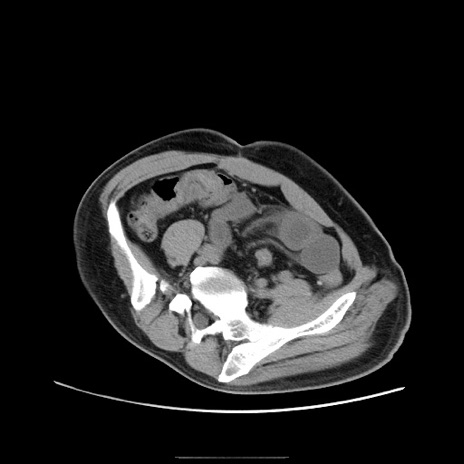

冠状断像

【症例】50歳代男性

【主訴】腹痛

【現病歴】AVMからの被殻出血のため回復期リハ病棟入院中。 本日午後3時頃急に下腹部痛が出現した。

【既往歴】AVM、被殻出血、虫垂炎、高血圧

【身体所見】意識晴明、左半身不全麻痺、会話の理解は良好、36.5°C、腹部:膨隆、全体に板状硬、下腹部正中に圧痛点あり、反跳痛-、筋性防御不明、右下腹部にope scar

【データ】WBC 9400、CRP 0.06